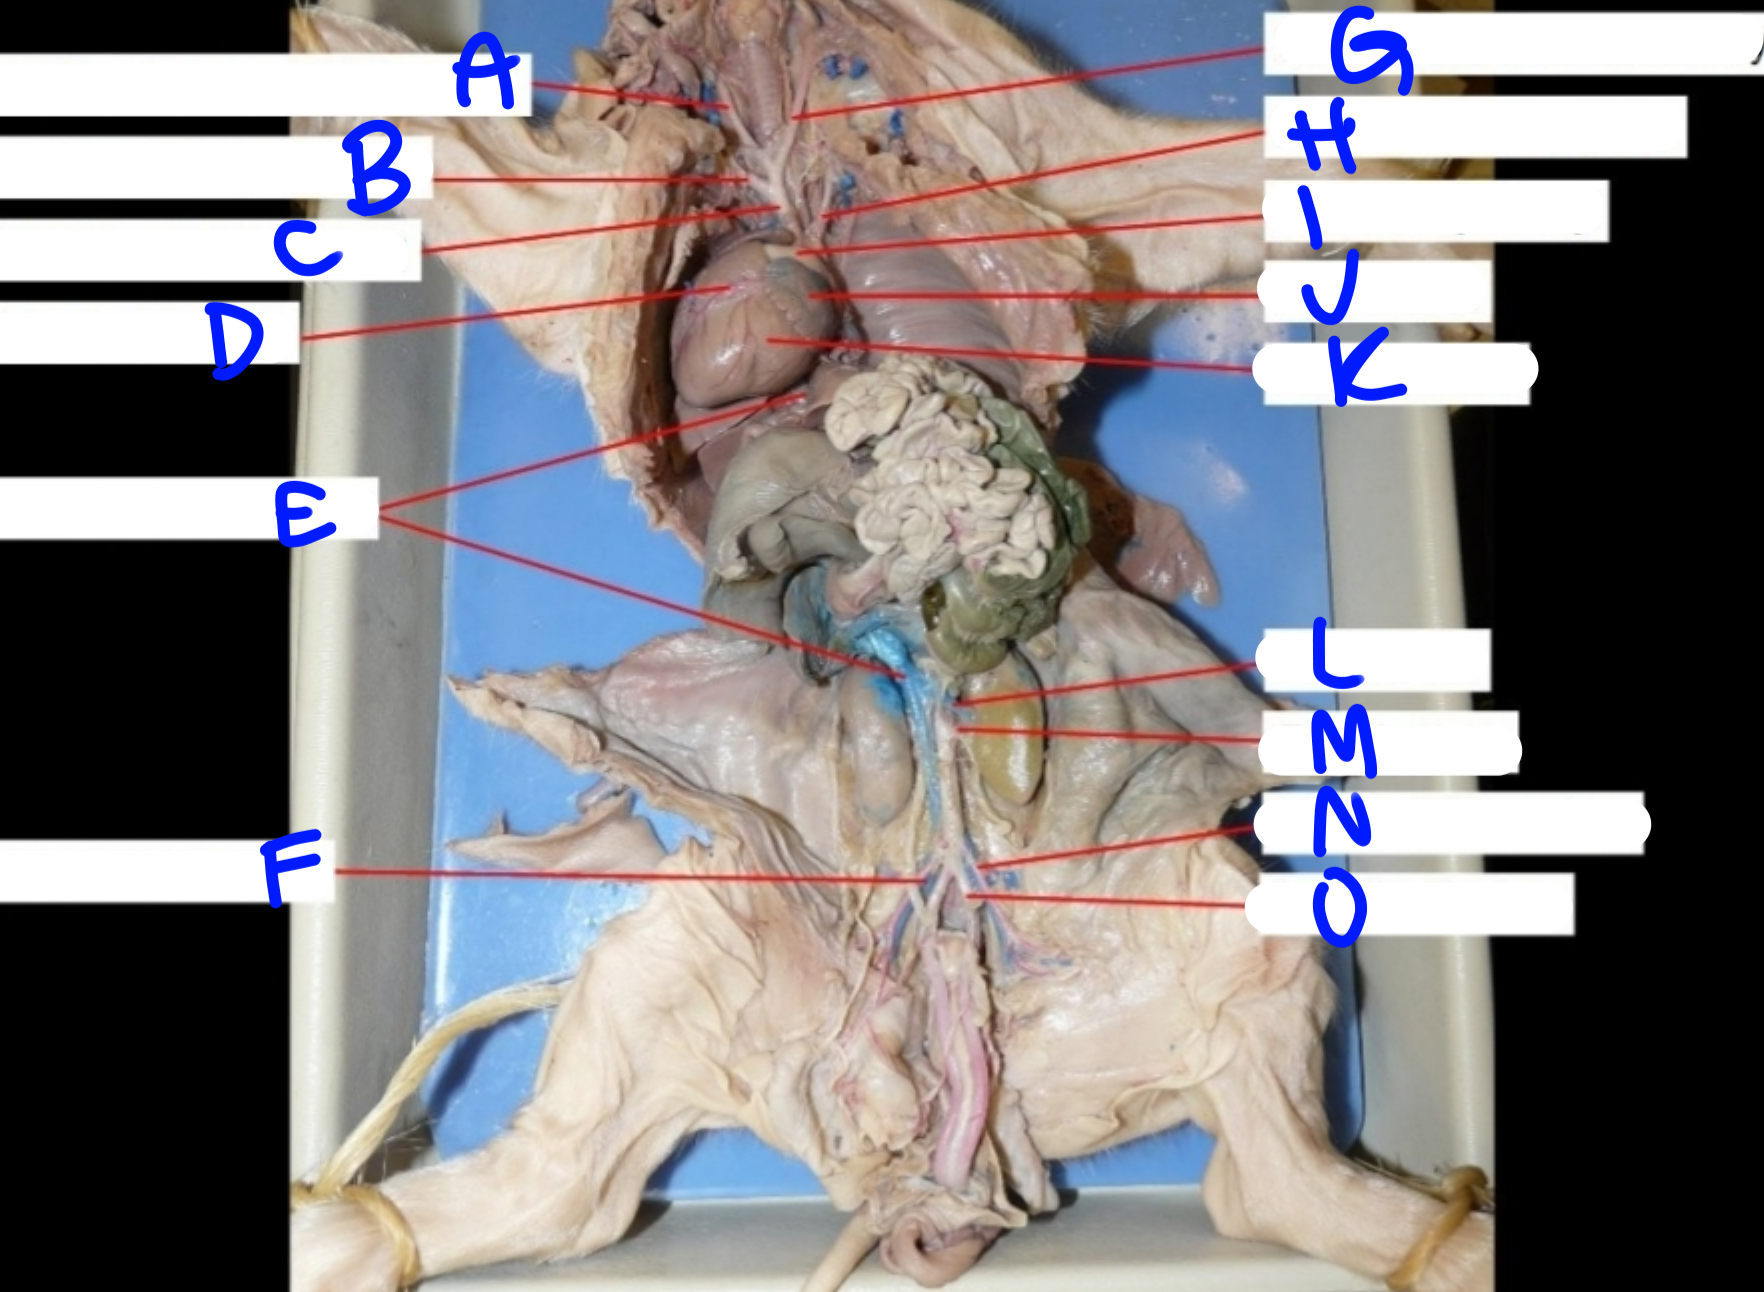

A

Right common carotid artery - delivers oxygenated blood to the head & neck

B

Right subclavian artery - delivers oxygenated blood to the upper body

C

Brachiocephalic artery - delivers oxygenated blood to the upper body

D

Coronary artery - delivers oxygenated blood to the heart

E

Posterior vena cava - carries deoxygenated blood from the lower body to the right side of the heart

G

Left common carotid artery - delivers oxygenated blood to the upper body

H

Left subclavian artery - carries oxygenated blood to the upper body

I

Pulmonary artery - delivers deoxygenated blood from the heart to the lungs

J

Left atrium - delivers oxygenated blood to the left ventricle

K

Left ventricle - delivers oxygenated blood to the systemic circuit

L

Renal vein - delivers blood from the kidney & ureter to the inferior vena cava

M

Renal artery - delivers blood from the kidney & ureter to the inferior vena cava

O

Umbilical artery - carries deoxygenated blood to the placenta